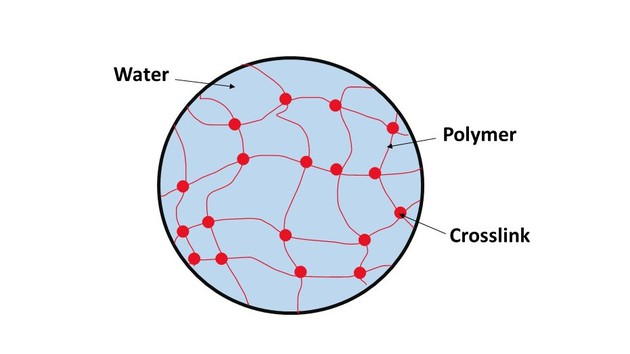

A nanogel is a polymer-based, crosslinked hydrogel particle on the sub-micron scale. It essentially combines the advantages of a hydrogel with nanoparticles. To understand nanogels we must first understand hydrogels. A hydrogel is a three-dimensional network formed by hydrophilic polymers through chemical (covalent or ionic bonds) or physical (hydrogen bonds, van der Waals force, physical entanglement) cross-linking. Hydrogels can swell (enlarge) and retain a significant fraction of water within their structure, but they will not dissolve in water. It is produced by the simple reaction of one or more monomers: a molecule that can be bonded to other identical molecules to form a polymer. Think of hydrogels as essentially a gel: they are stable yet still possess a fluid and free-flowing quality.

The ability of hydrogels to absorb water arises from hydrophilic (tending to interact with water) functional groups attached to its backbone, while their resistance to dissolution arises from cross-links between network chains. Hydrogels are also stable in conditions of sharp and strong fluctuations in temperature.

Along with those advantages, natural polymers are ideal skeletons for hydrogels because of their diversified properties such as their biocompatibility, biodegradability, and environmental friendliness. Natural polymers can be defined as polymers that are formed from photosynthesis, biochemical reactions in the natural world, or extracted from natural products. Hydrogels based on natural polymers (eg., alginate, starch, cellulose, chitosan, gelatin, collagen, hyaluronic acid) show good degradability, biocompatibility, nontoxic degradation products, good flexibility similar to natural tissue, and are in natural abundance.

Biocompatibility is one of the most significant characteristics of hydrogels for biomedical applications, referring to the ability of a material to connect with bodily organs with minimum damage to the surrounding tissues and without triggering undesirable immune responses. Hydrogels based on natural polymers usually have excellent biocompatibility due to the intrinsic properties of natural polymers.

Biodegradability, the capacity of a substance to break down after interactions with biological elements, is another essential property of hydrogel materials for biomedical applications. Most hydrogels made from natural polymers can be broken down by enzymes. The speed at which these hydrogels decompose depends on factors such as the polymer’s molecular weight and whether the polymer is more amorphous (lacking a clearly defined shape) or crystalline (having the structure/form of a crystal), and if it is hydrophilic or hydrophobic.

Now that we understand the importance of hydrogels, lets return to nanogels. A nanogels characteristics, such as size, charge, porosity, amphiphilicity, softness, and degradability, can be fine-tuned by varying their chemical composition. They can be designed in a spherical shape or in a more porous structure, with holes in their shape. From a drug delivery perspective, this essentially allows us to design the system based on how we want the drug to be released. Based on the structure, drugs can be released in different orders. For example, in a spherical shape, the outermost contained drug would be released first; however, in a porous structure, you could theoretically have the innermost structure released first. The porous structure is sort of like Swiss cheese in that there are ways to get to the middle of the structure, allowing you to theoretically release drugs from the inside out.